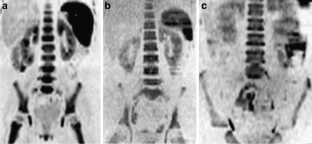

Fig. 2